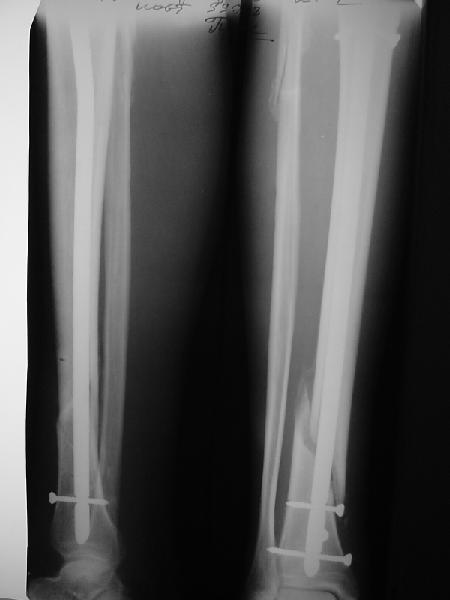

На мой взгляд, на снимках, приведённых Вами - неправильно сростающийся перелом дистальной трети большеберцовой кости, состояние после остеосинтеза интрамедуллярным гвоздём.

Как Вы пишите снимок под номером 1 - менсяц после операции, под номером 2- два месяца после операции.

Ok. А также и следующий, в 3 месяца.

Это наглядная демонстрация возможности ранней полной нагрузки при нестабильном по оси повреждении, причем не в самых благоприятных механических условиях - при плохом сопоставлении, со слабым фиксатором.

Сверху - один статический винт, а снизу - три. Что раньше сломается? Конечно, он потом и нижние сломал, и Вы правы, если бы верхний динамичесий винт уже уперся бы в нижний край отверстия, будь гвоздь подлинее, перфорировал бы сустав как пить дать.

Как я уже говорил, мы сделали выводы из этого и других подобных случаев. Очевидно, решений проблемы два - либо уменьшить нагрузку, либо увеличить прочность фиксатора. Первое решение работает не со всеми больными, так что пошли по второму пути - мы больше не используем гвозди с запирающими винтами диаметром 4 мм.